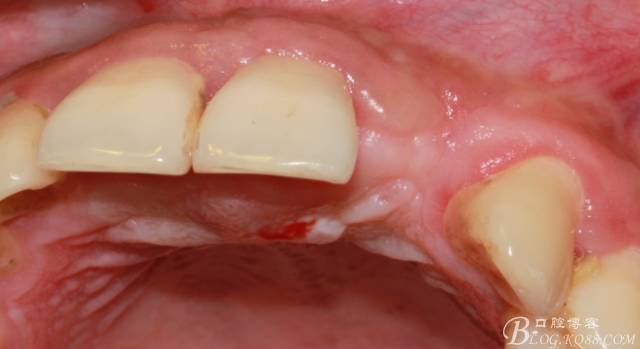

4個月后,唇側(cè)豐滿度尚可,與鄰牙之間齦乳頭完整。

保留齦乳頭翻小瓣。